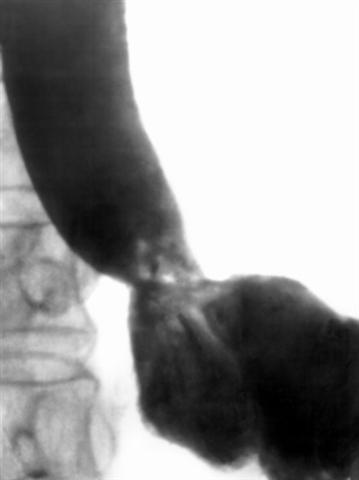

Рис. 3в). Ренгенограммы пищевода при сужении его поддиафрагмального сегмента: после дилатации (просвет поддиафрагмального сегмента пищевода расширен).